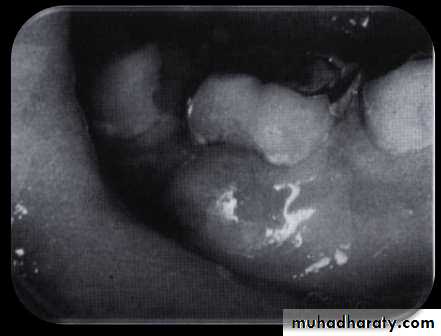

• Periodontal pockets around lower anterior teeth, showing rolled margins, edematous inflammatory changes and abundant calculus